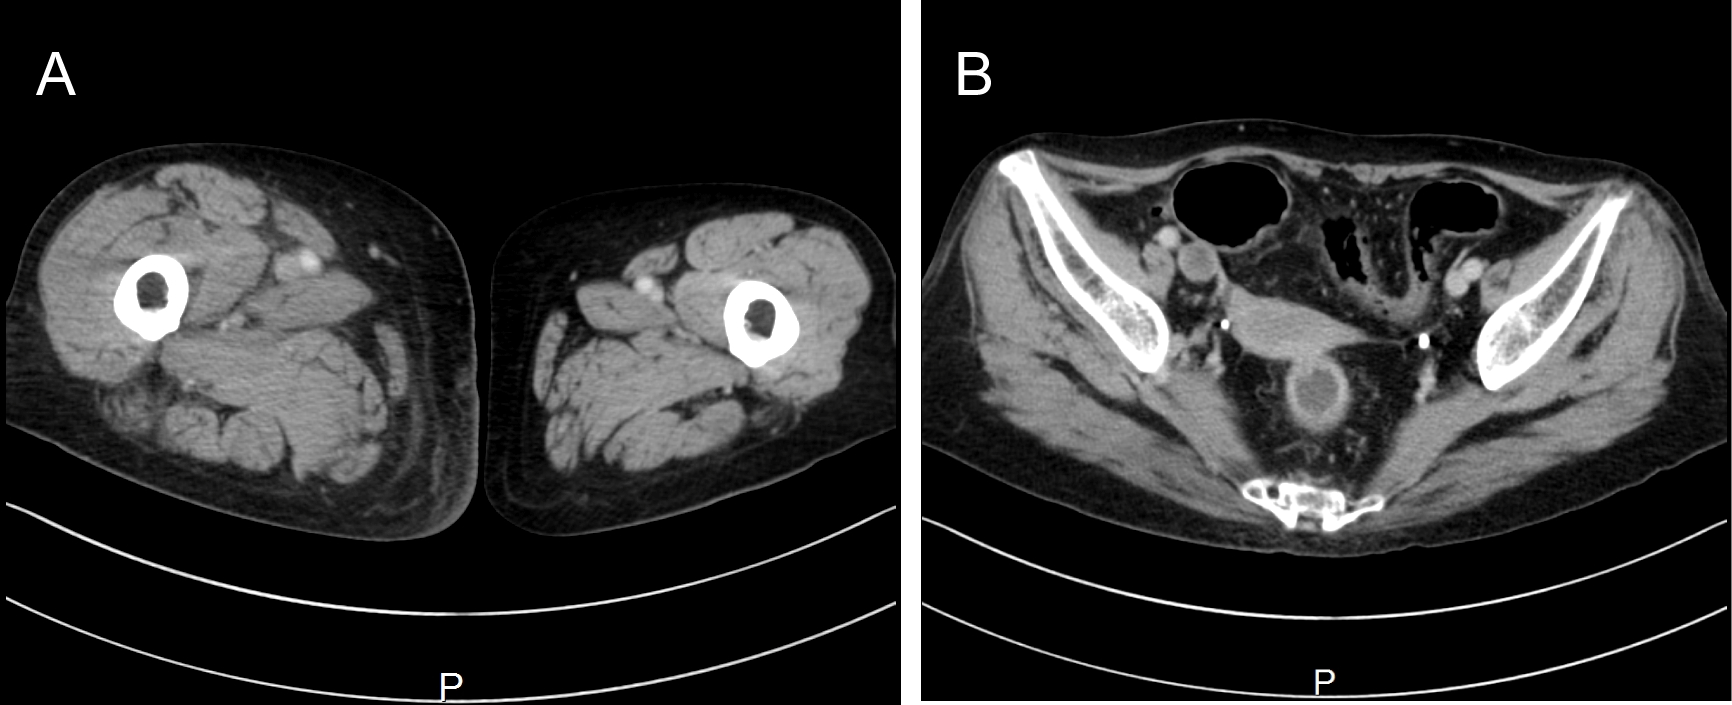

Patient case 1 was placed a right inguinal catheter and had swelling and flares on her right lower extremity after 12 days of catheter placement. Computed-tomography scans revealed a wide range of thrombus formation over the right femoral vein to inferior vena cava (Figure 1). We immediately placed an inferior vena cava filter (Figure 2) via the jugular vein and initiated thrombolytic therapy. Patient case 3 was placed a right jugular catheter and showed signs of sepsis; therefore, we removed the catheter on the third day. A thrombus was found on the catheter tip. Acinetobacter was also detected by culture of patient blood and the catheter tip. The patient's fever was improved after catheter withdrawal. Patient case 5 was placed a right jugular catheter and developed remittent fever after the initial LA. We administrated antibiotics and removed the catheter. Thrombus was observed on the tip of catheter. Blood culture and culturing the catheter tip were negative. However, remittent fever was improved after catheter removal. All patients recovered without any after effects.

Figure 1: CT scan reveals a swollen right lower extremity (1-a) and filling defect showed thrombosis in the right iliac vein (1-b). View Figure 1